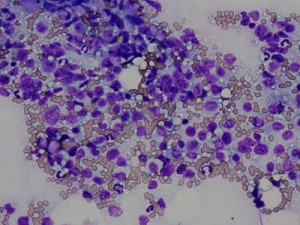

脾臓の針吸引生検で採取された細胞です。

血液成分を背景に多数の中〜大型のリンパ系細胞が採取され、腹腔内(脾臓)低分化型リンパ腫と診断されました。

同時におこなった(※)猫リンパ球クロナリティ検査ではB細胞のクロナリティが確認されました。